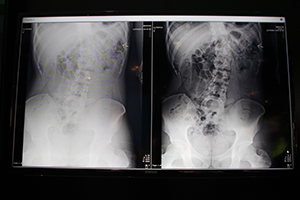

同社が行った胸部,腹部を想定したCD-RADファントムと人体を想定したアクリル板を用いた検証では,80kVでグリッドあり,グリッドなし,Virtual Gridでの計測を行ったところ,Virtual Gridでの低線量での画質の画質指数(IQF)が向上することが確かめられたという。展示では,Virtual Gridによる画質の向上の効果について,胸部や腹部の臨床画像を示して,実際の低線量撮影における画質の向上をアピールした。

Virtual Grid(右)による臨床画像(日本人の腹部) |

大柄なアメリカ人の腹部画像。 |